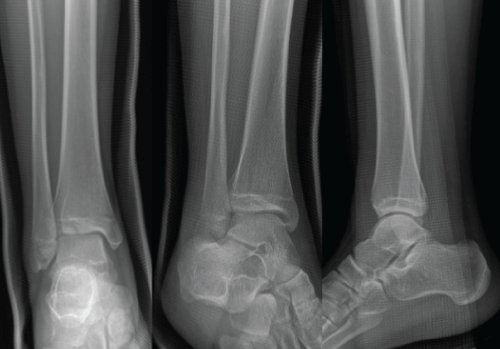

A 21-year-old female was presented in our emergency department for a painful right ankle. She had injured the ankle a day earlier while snowboarding. Examination of her ankle revealed mild pain on the range of movement, no tenderness over medial and lateral aspect of her ankle. The post injury radiographs were generally normal (Figure 5). However, her CT scan of the ankle revealed a Volkmann fracture (Figure 6).

Figure 5: Plain radiographs of the injured ankle. AP and mortise views did not show any bony injuries. (a and b) the medial clear space was less than 4 mm; (c) there was no sagittal plane instability of her ankle on lateral view.

Figure 6: CT scans revealed posterolateral avulsion fracture but no displacement was noticed and no syndesmotic incongruency.